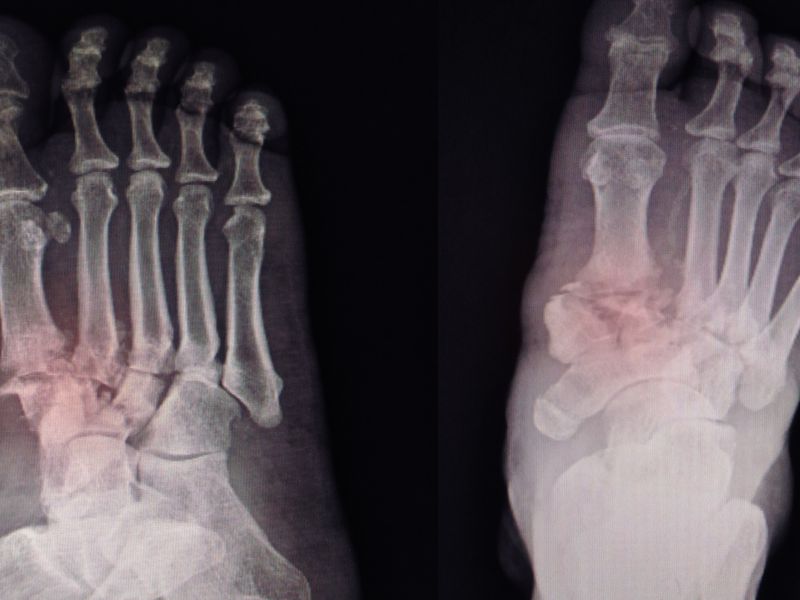

对于骨折的人来说,康复的过程是属于非常漫长的一个过程,在这个过程当中一定要注意自己的饮食情况,因为正确的饮食不仅可以及时为身体补充营养,还能促进骨折的愈合,缩短病程的发展。那么下面就来了解一些关于骨折饮食方面的知识,希望可以起到一定的帮助。